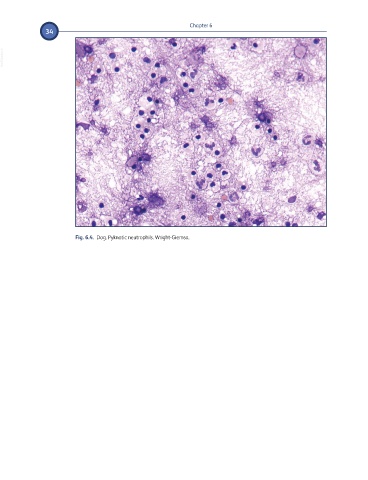

Fig. 6.4.  Dog. Pyknotic neutrophils. Wright-Giemsa.